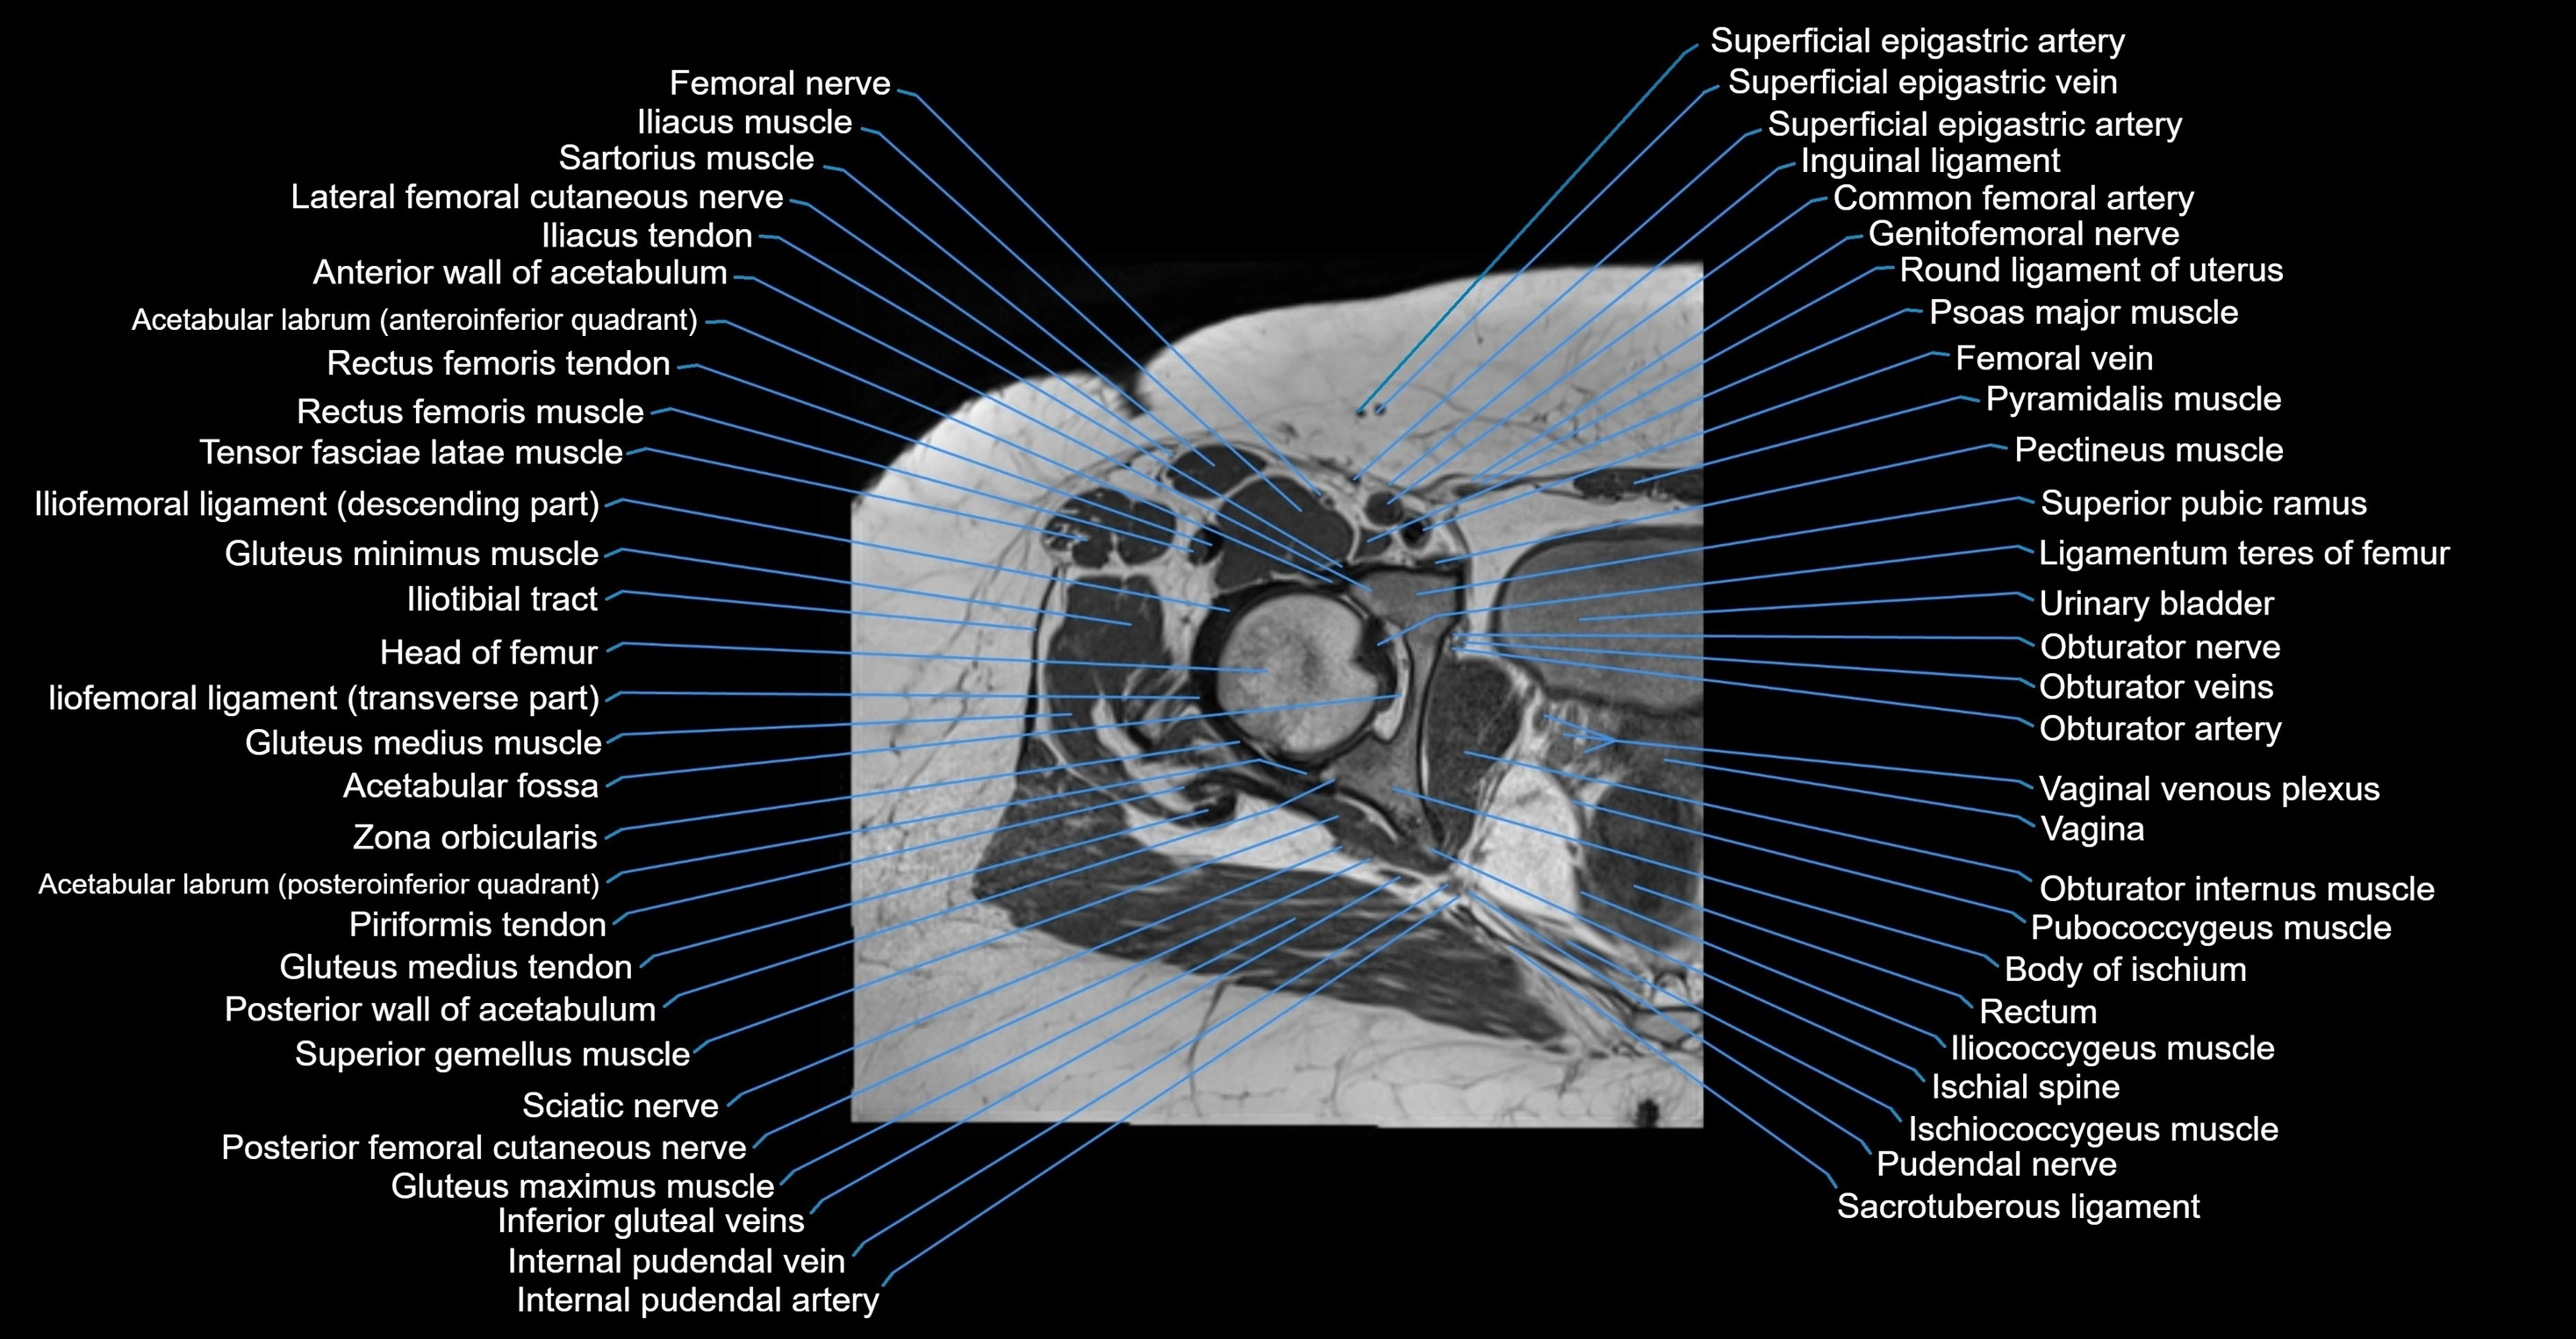

- Acetabular labrum

- Acetabulum

- Femoral nerve

- Femoral vein

- Gluteus maximus muscle

- Gluteus medius muscle

- Gluteus minimus muscle

- Head of femur

- Iliococcygeus muscle

- Iliopsoas muscle

- Ischial spine

- Ischiococcygeus muscle

- Obturator internus muscle

- Obturator nerve

- Obturator veins

- Pectineus muscle

- Pubococcygeus muscle

- Pudendal nerve

- Rectum

- Sacrotuberous ligament

- Tensor fasciae latae muscle

- Urinary bladder

- Vagina

- Vaginal venous plexus